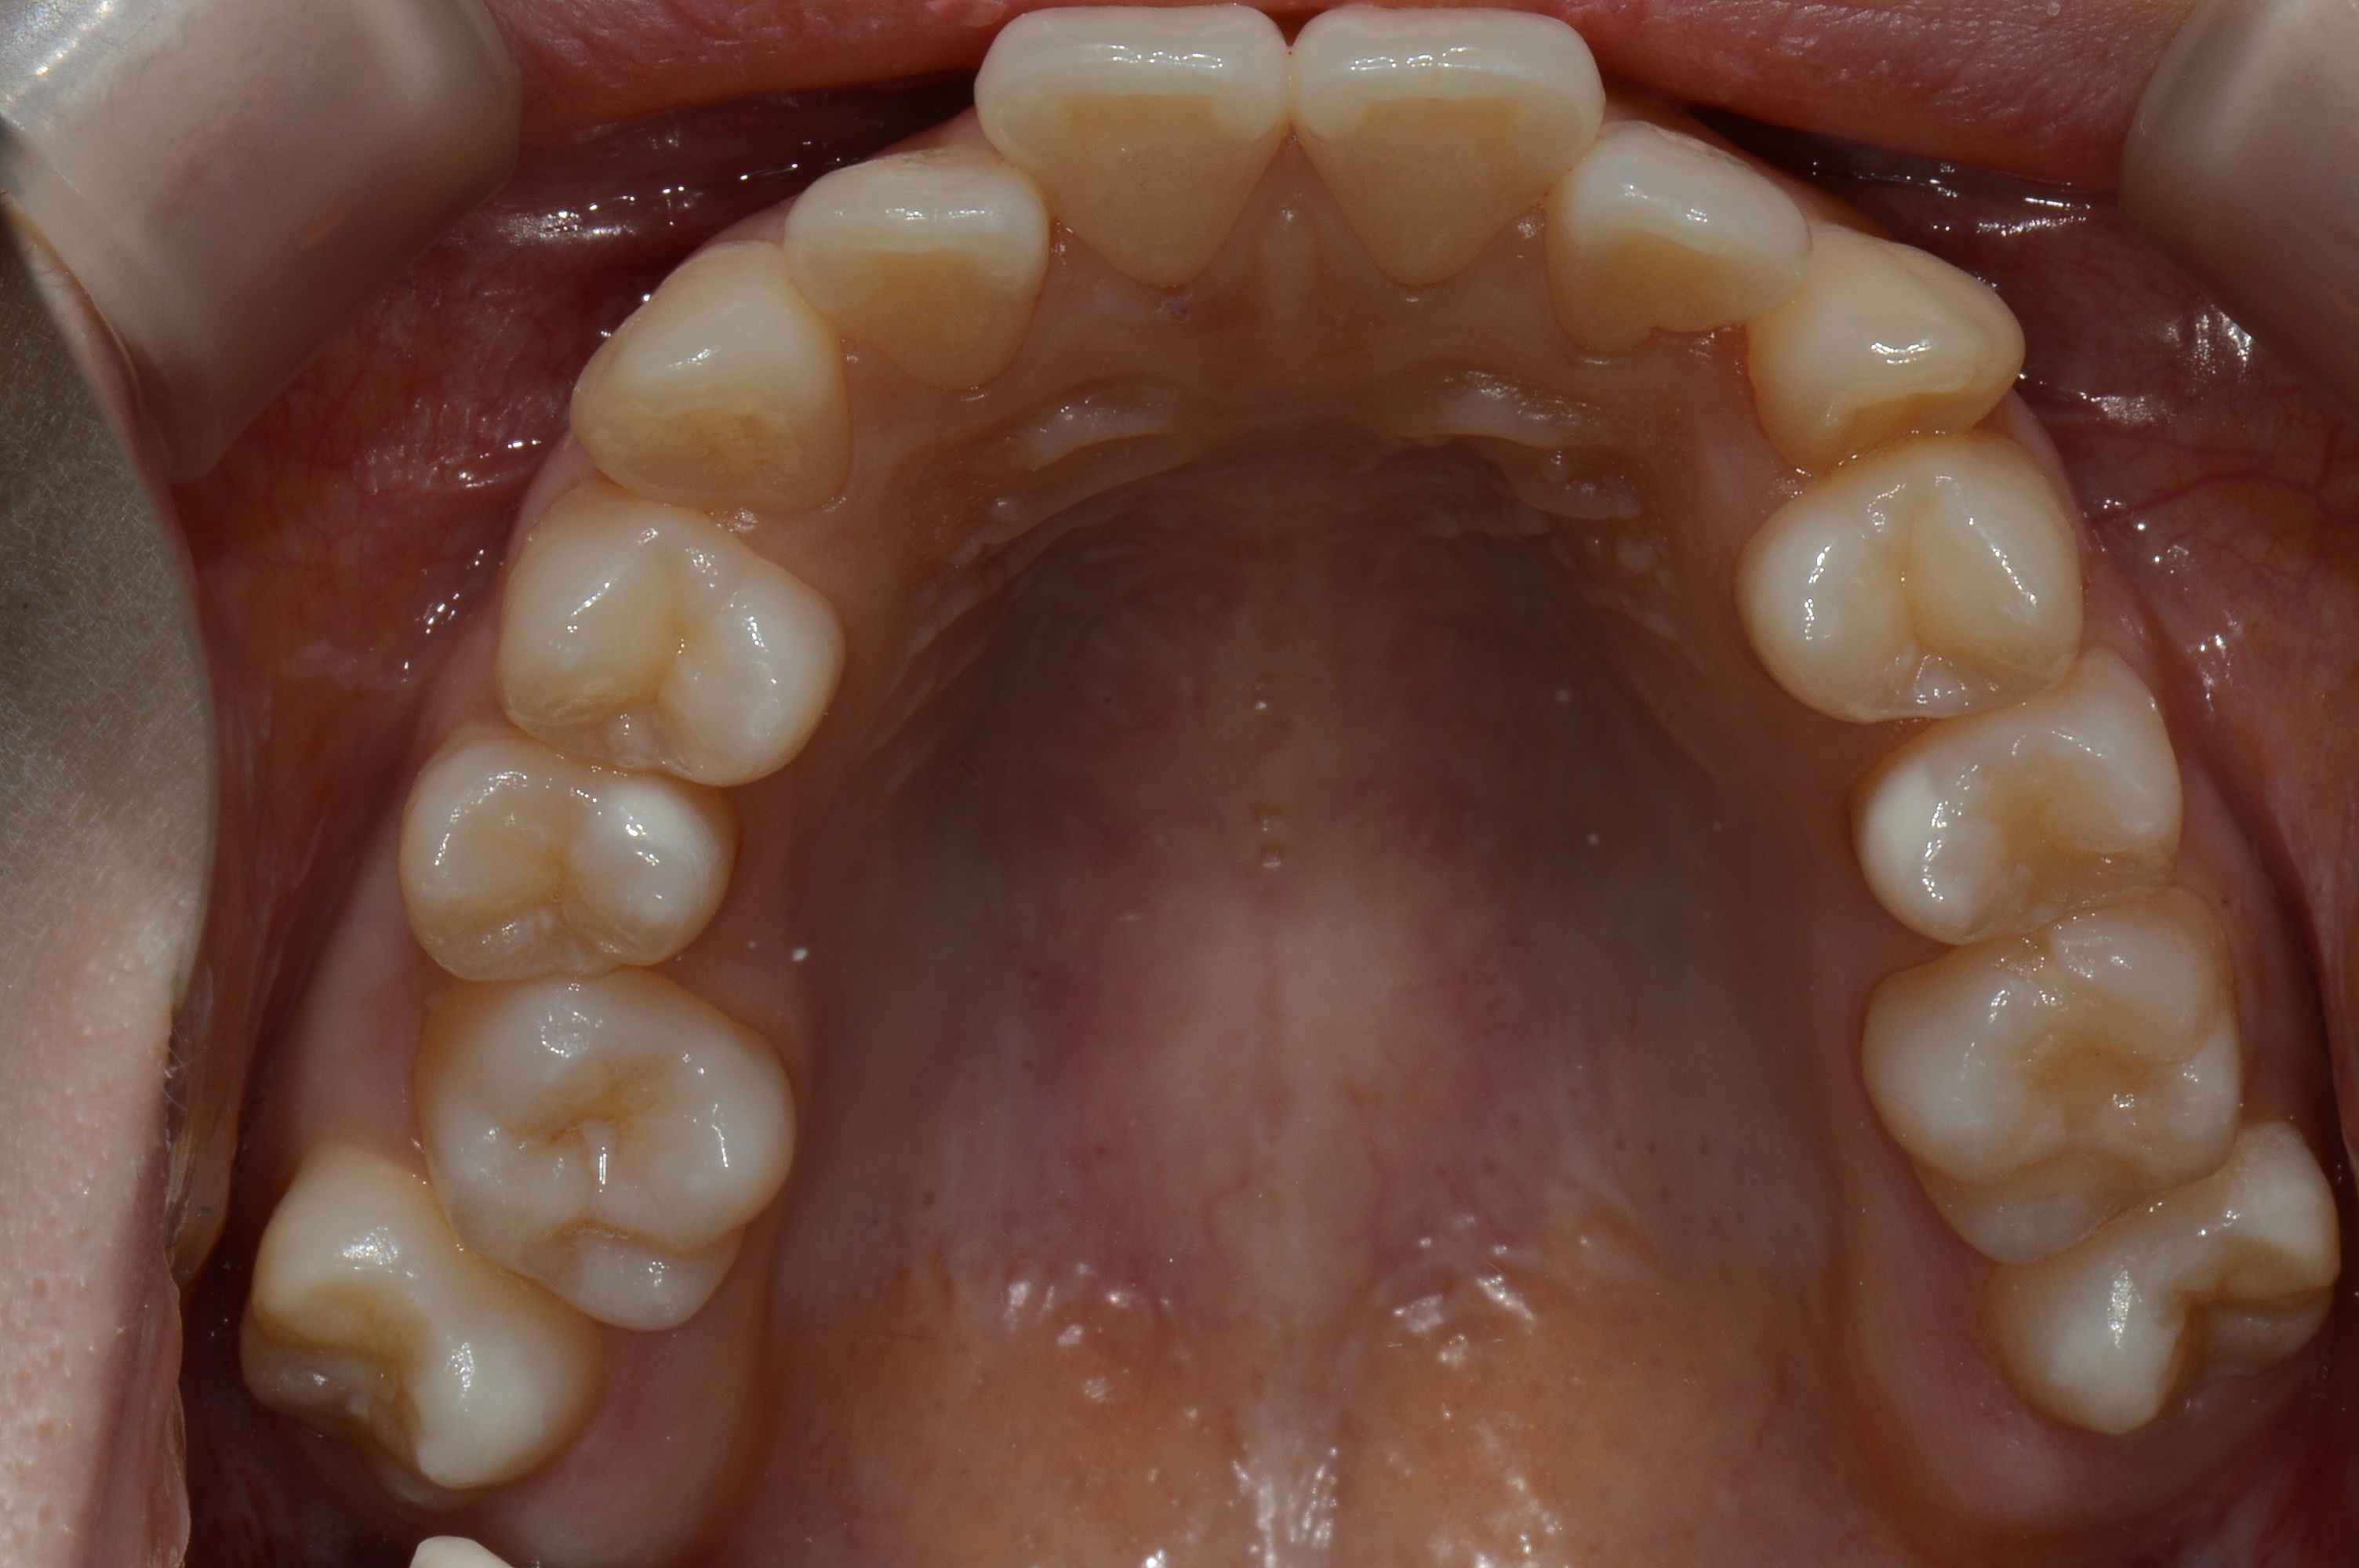

치료 후 사진입니다.